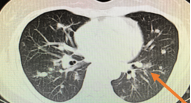

2018年5月4日胸部CT:

2018年6月8日胸部CT:

4.双肺转移灶较前稍增大。